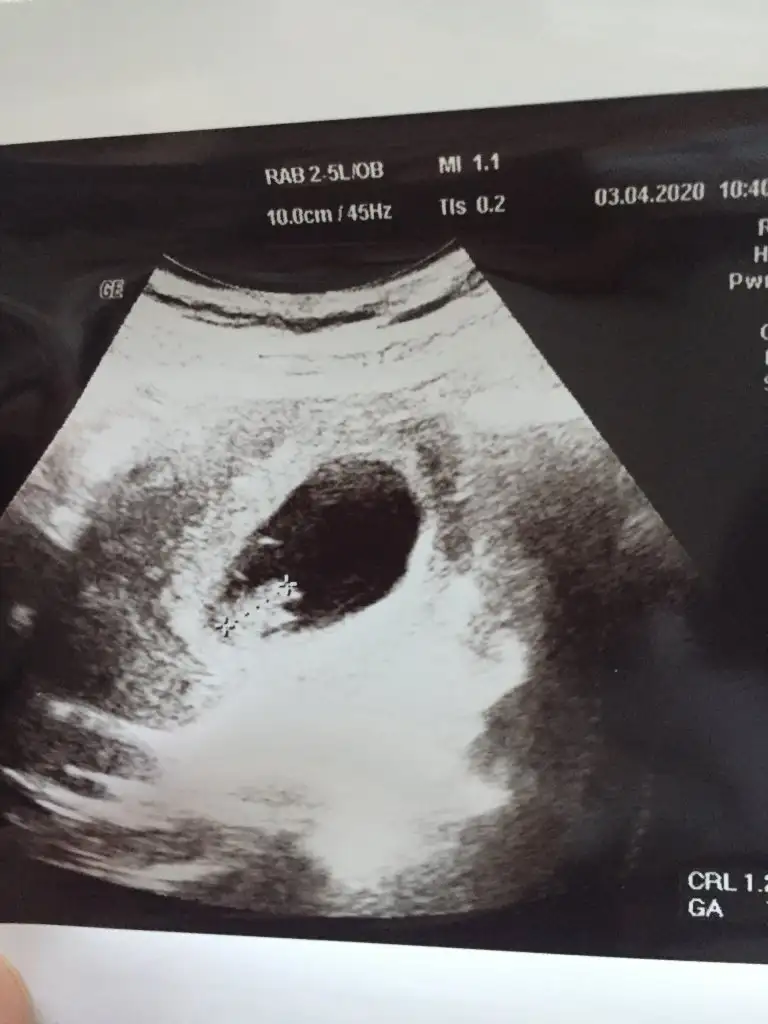

Merhaba banada bi tahmin yapabilirmisiniz acaba en son 7+6 da gittim dr simdi 12+1 ama wirus yuzunden gidemiyorumRamzi teorisine göre ( bilimsel bir araştırma sonucuymuş ve %85 doğruluğu varmış). İlk 6-8 haftalık ultrason görüntüsüne göre bebeğin kesenin içersinde soldan ya da sağdan girişine göre cinsiyet tahmini yapılıyor. Bilimsel olunca tecrübeli annelerimiz yada anne adaylarımızdan yardım istiyoruz. Doğruluğu var mı öğrenmek adına :) Bizleri aydınlatırsanız çok seviniriz. bu teorieye göre;

Yolksac sagda buna göre kız vajinal bakıldı ise erkekMerhaba banada bi tahmin yapabilirmisiniz acaba en son 7+6 da gittim dr simdi 12+1 ama wirus yuzunden gidemiyorum Eki Görüntüle 2612214

Kaç haftalık 6-7 hafta olmalı kese içinBanada bi tahminde bulunabilirmisiniz